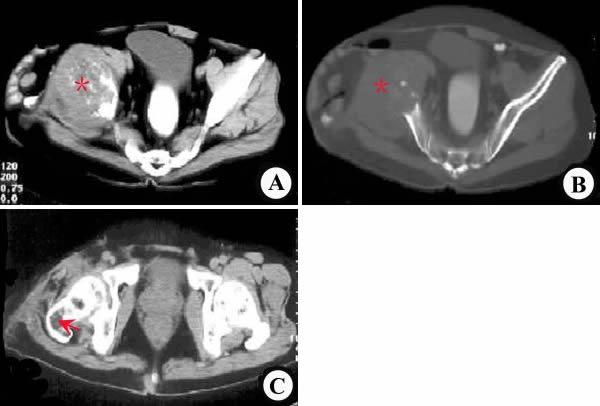

骨盆、股骨多发骨转移瘤-CT

【CT图片】:

【影像表现】:CT平扫软组织窗(A、 C)、骨窗(B)示右侧髂骨溶骨性骨破坏区及软组织肿块(A、B,*),右侧股骨低密度骨破坏(C,↑)。

【影像诊断】:骨盆、股骨多发骨转移瘤。